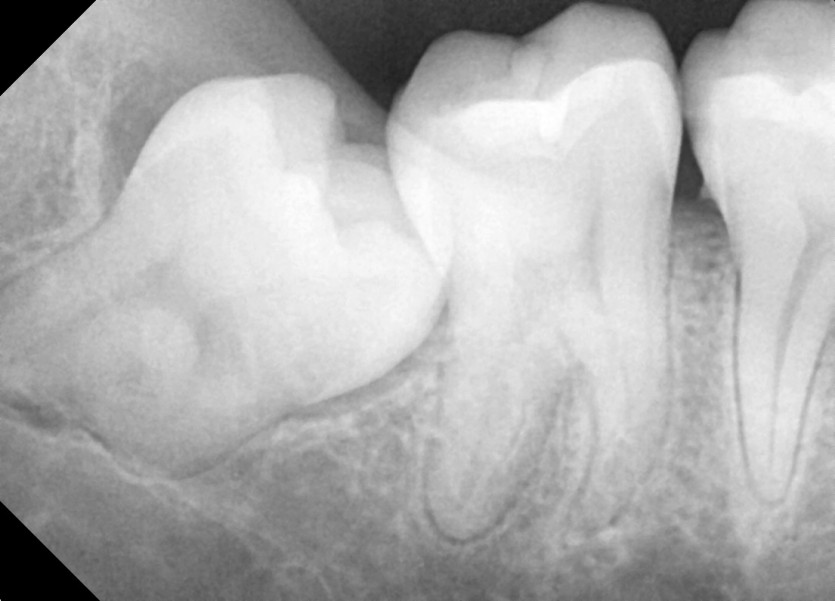

#28,38,48 사랑니 발치

구강 외과 전문의가 당일 발치했습니다.